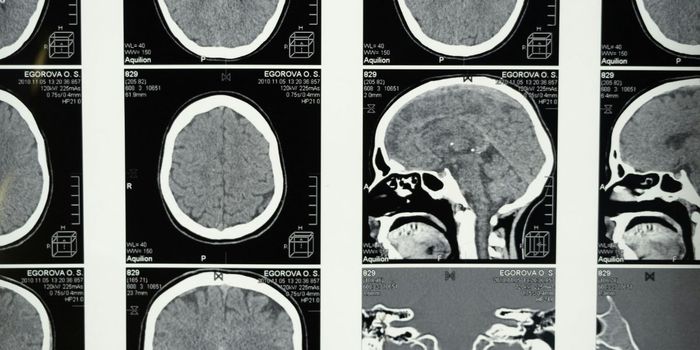

SEP 09, 2024NeuroscienceAlzheimer's patients with high levels of tau and amyloid-beta experience faster cognitive decline.

JUL 29, 2024NeuroscienceA blood test can detect Alzheimer's disease (AD) more accurately than traditional diagnostic methods.